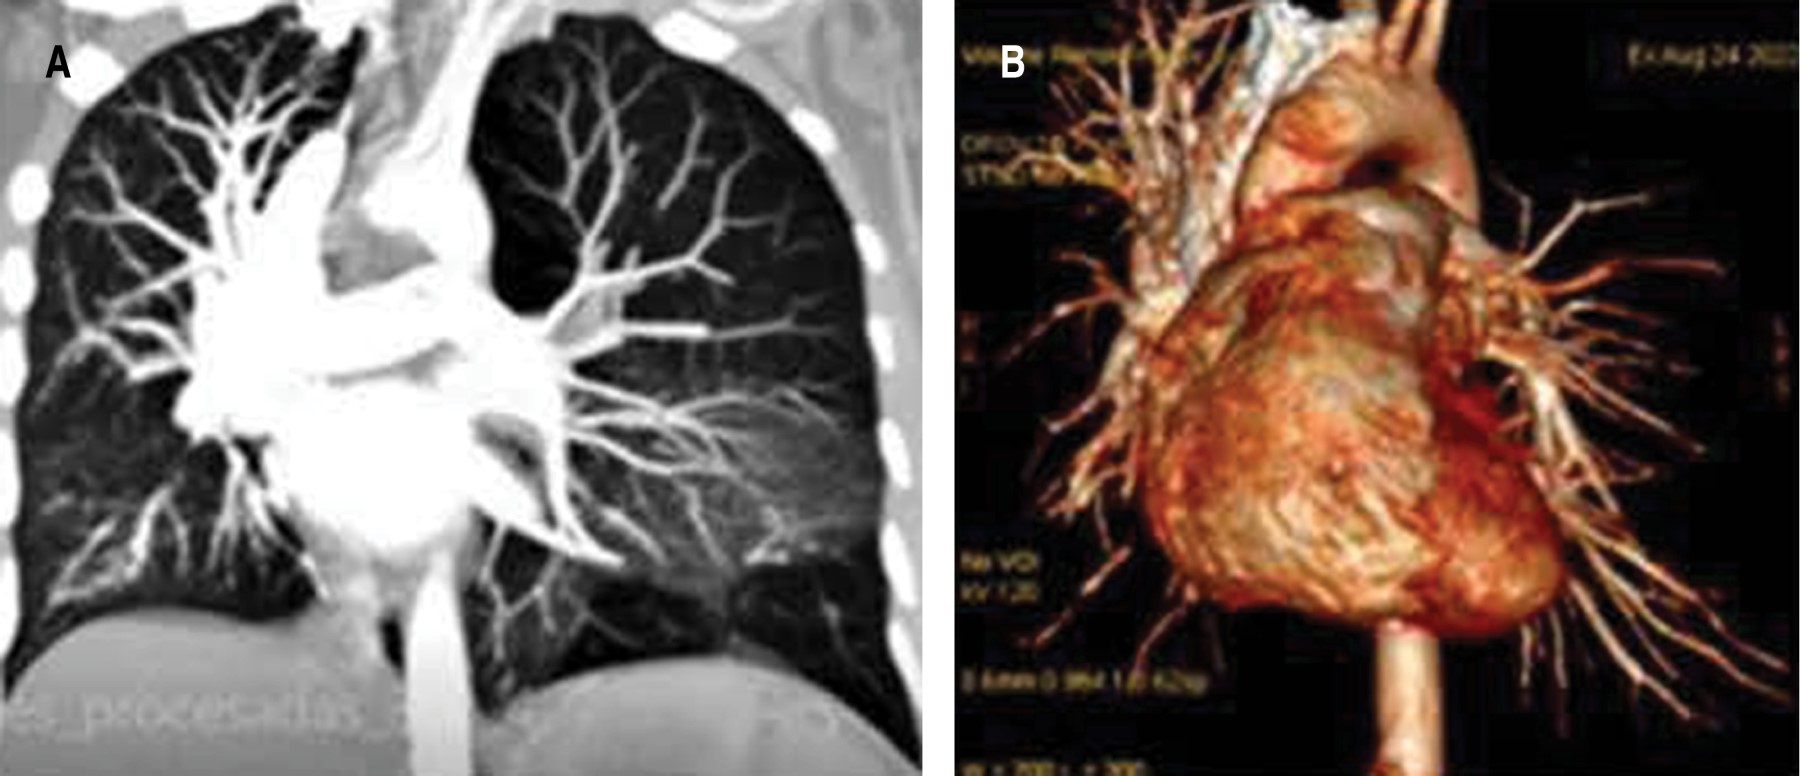

Descartando probable tromboembolia pulmonar (TEP), se solicita angioTAC, la cual no muestra datos de TEP en las reconstrucciones digitales, mostrando continuidad de opacificación de arterias pulmonares de primer y segundo orden. Pulmón con hiperclaridad izquierda e hipoplasia de la arteria pulmonar ipsilateral que mide 9 mm en diámetro A-P en comparación a 20 mm de la derecha. Considerar síndrome de Swyer James MacLeod (Figura 2). El ecocardiograma, informa dextrocardia con FE en 55%. Baja probabilidad de HPA con presión sistólica pulmonar en 20 mmHg. La TAC abdominal no reporta anomalías.

Un leve dolor en el tórax motivó su consulta y la radiografía mostró el pulmón izquierdo hiperlúcido. Se diagnostica con mayor frecuencia en la infancia, típicamente ocurre en niños menores de ocho años, antes que el pulmón haya completado el desarrollo y la maduración pulmonar.5 Puede cursar de forma asintomática hasta la edad adulta, presentarse con neumotórax espontáneo generalmente asintomático,2 o como condición poco frecuente de emergencia,3 como bula calcificada6 y con transfiguración placentaria del parénquima pulmonar.7 La radiografía y tomografía de tórax de la paciente, mostraron pulmón segmentario hiperlúcido con alteración de la vascularidad, lo que normalmente describen otros autores como hiperclaridad pulmonar unilateral o lobar, asociada a atrapamiento aéreo del pulmón hiperclaro durante la espiración.2,5,8 A fin de descartar el diagnóstico diferencial de tromboembolia pulmonar se solicitó angiotomografía, la cual demostró las anomalías anatómicas de la arteria pulmonar izquierda con un menor calibre y disminución del flujo. El patrón espirométrico evidenció proceso restrictivo. No se realizó gammagrafía pulmonar que pudiera mostrar la disminución de la ventilación del pulmón patológico secundario a cambios enfisematosos y una marcada disminución de la perfusión, como consecuencia del menor calibre de la arteria pulmonar.5,8 Por lo tanto, los criterios de diagnóstico para este síndrome requieren uno de los siguientes hallazgos: a) pérdida unilateral del volumen pulmonar con hiperlucencia demostrada por radiografía de tórax; b) reducción unilateral de la vascularización en una tomografía computarizada del tórax; y c) pérdida de perfusión unilateral en gammagrafía pulmonar con tecnecio-99m.1,2